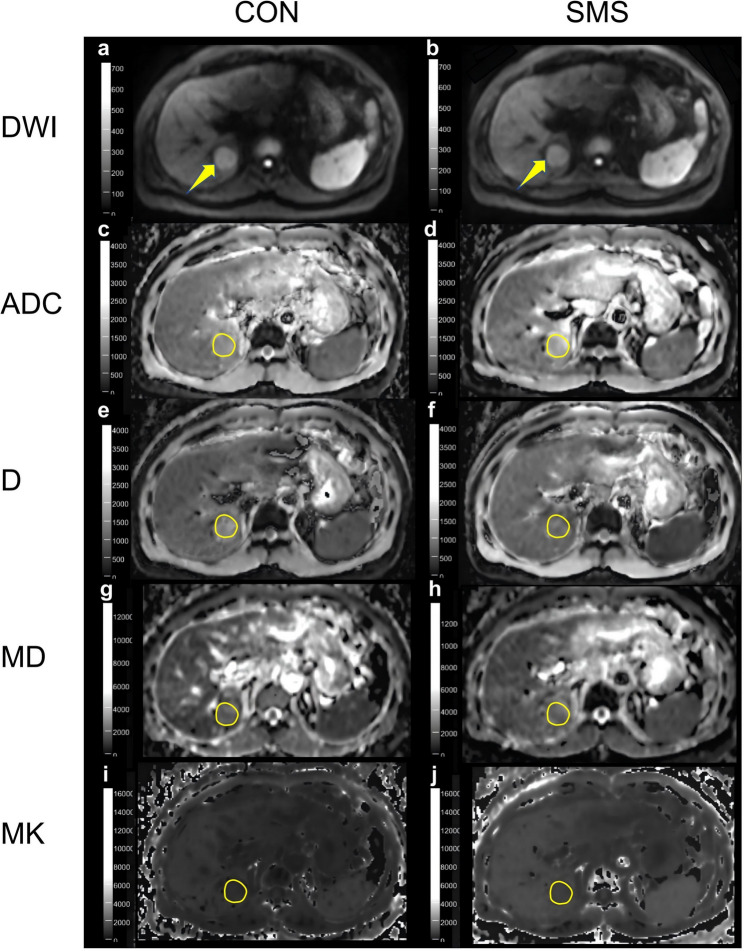

Materials and methods: A prospective study was conducted with 77 HCC patients. Diffusion-weighted imaging (DWI), IVIM, and DKI were performed on a 3T MRI using both SMS and conventional sequences. The values of diffusion parameters (ADC, D, D*, f, MD, and MK) were compared among SMS and conventional sequences, between MVI-positive and MVI-negative groups, and between high-grade and low-grade HCC groups. Receiver operating characteristic (ROC) curves were used to assess the diagnostic performance of diffusion parameters in predicting MVI and histologic grade. Inter-reader consistency was evaluated using intraclass correlation coefficients (ICC).

Results: Among the 77 patients, 29.9% were MVI-positive and 35.1% had high-grade HCC. SMS reduced scanning time by up to 44.44%. Most diffusion parameters were similar between SMS and conventional sequences, except for slightly lower ADC and f in SMS. MVI-positive and high-grade HCC cases showed lower ADC, D, D*, and MD values and higher MK values. The ICC ranged from 0.702 to 0.879. SMS-MK demonstrated the highest diagnostic performance with an AUC of 0.92 for MVI and 0.86 for histologic grade.